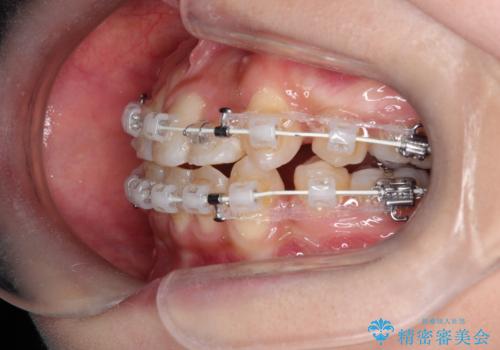

- 患者様は、歯並びのガタガタ(重度の叢生)を改善したいとのことで来院されました。診察すると、歯列のスペース不足が著しく、前歯が重なり合い、噛み合わせにも影響が出ている状態でした。歯をきれいに並べるためには抜歯によるスペース確保が不可欠と判断し、上下の小臼歯4本を抜歯したうえで、目立ちにくい審美ワイヤー矯正(白いワイヤーと透明ブラケット)を用いた治療計画を立てました。

抜歯によって歯を動かすためのスペースを確保。その後、審美ワイヤー矯正を用いて歯を1本ずつ適切な位置に誘導しながら、噛み合わせのバランスも整えていきました。時間はかかりましたが、ガタガタの歯並びがきれいに整い、機能的にも審美的にも満足のいく仕上がりとなりました。患者様からは「歯並びが劇的に改善し、見た目だけでなく噛みやすさも向上した」と喜びの声をいただきました。